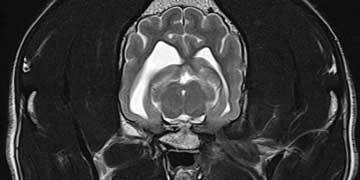

Scanner

Le Scanner

Concilier performance, coût raisonnable et risque modéré